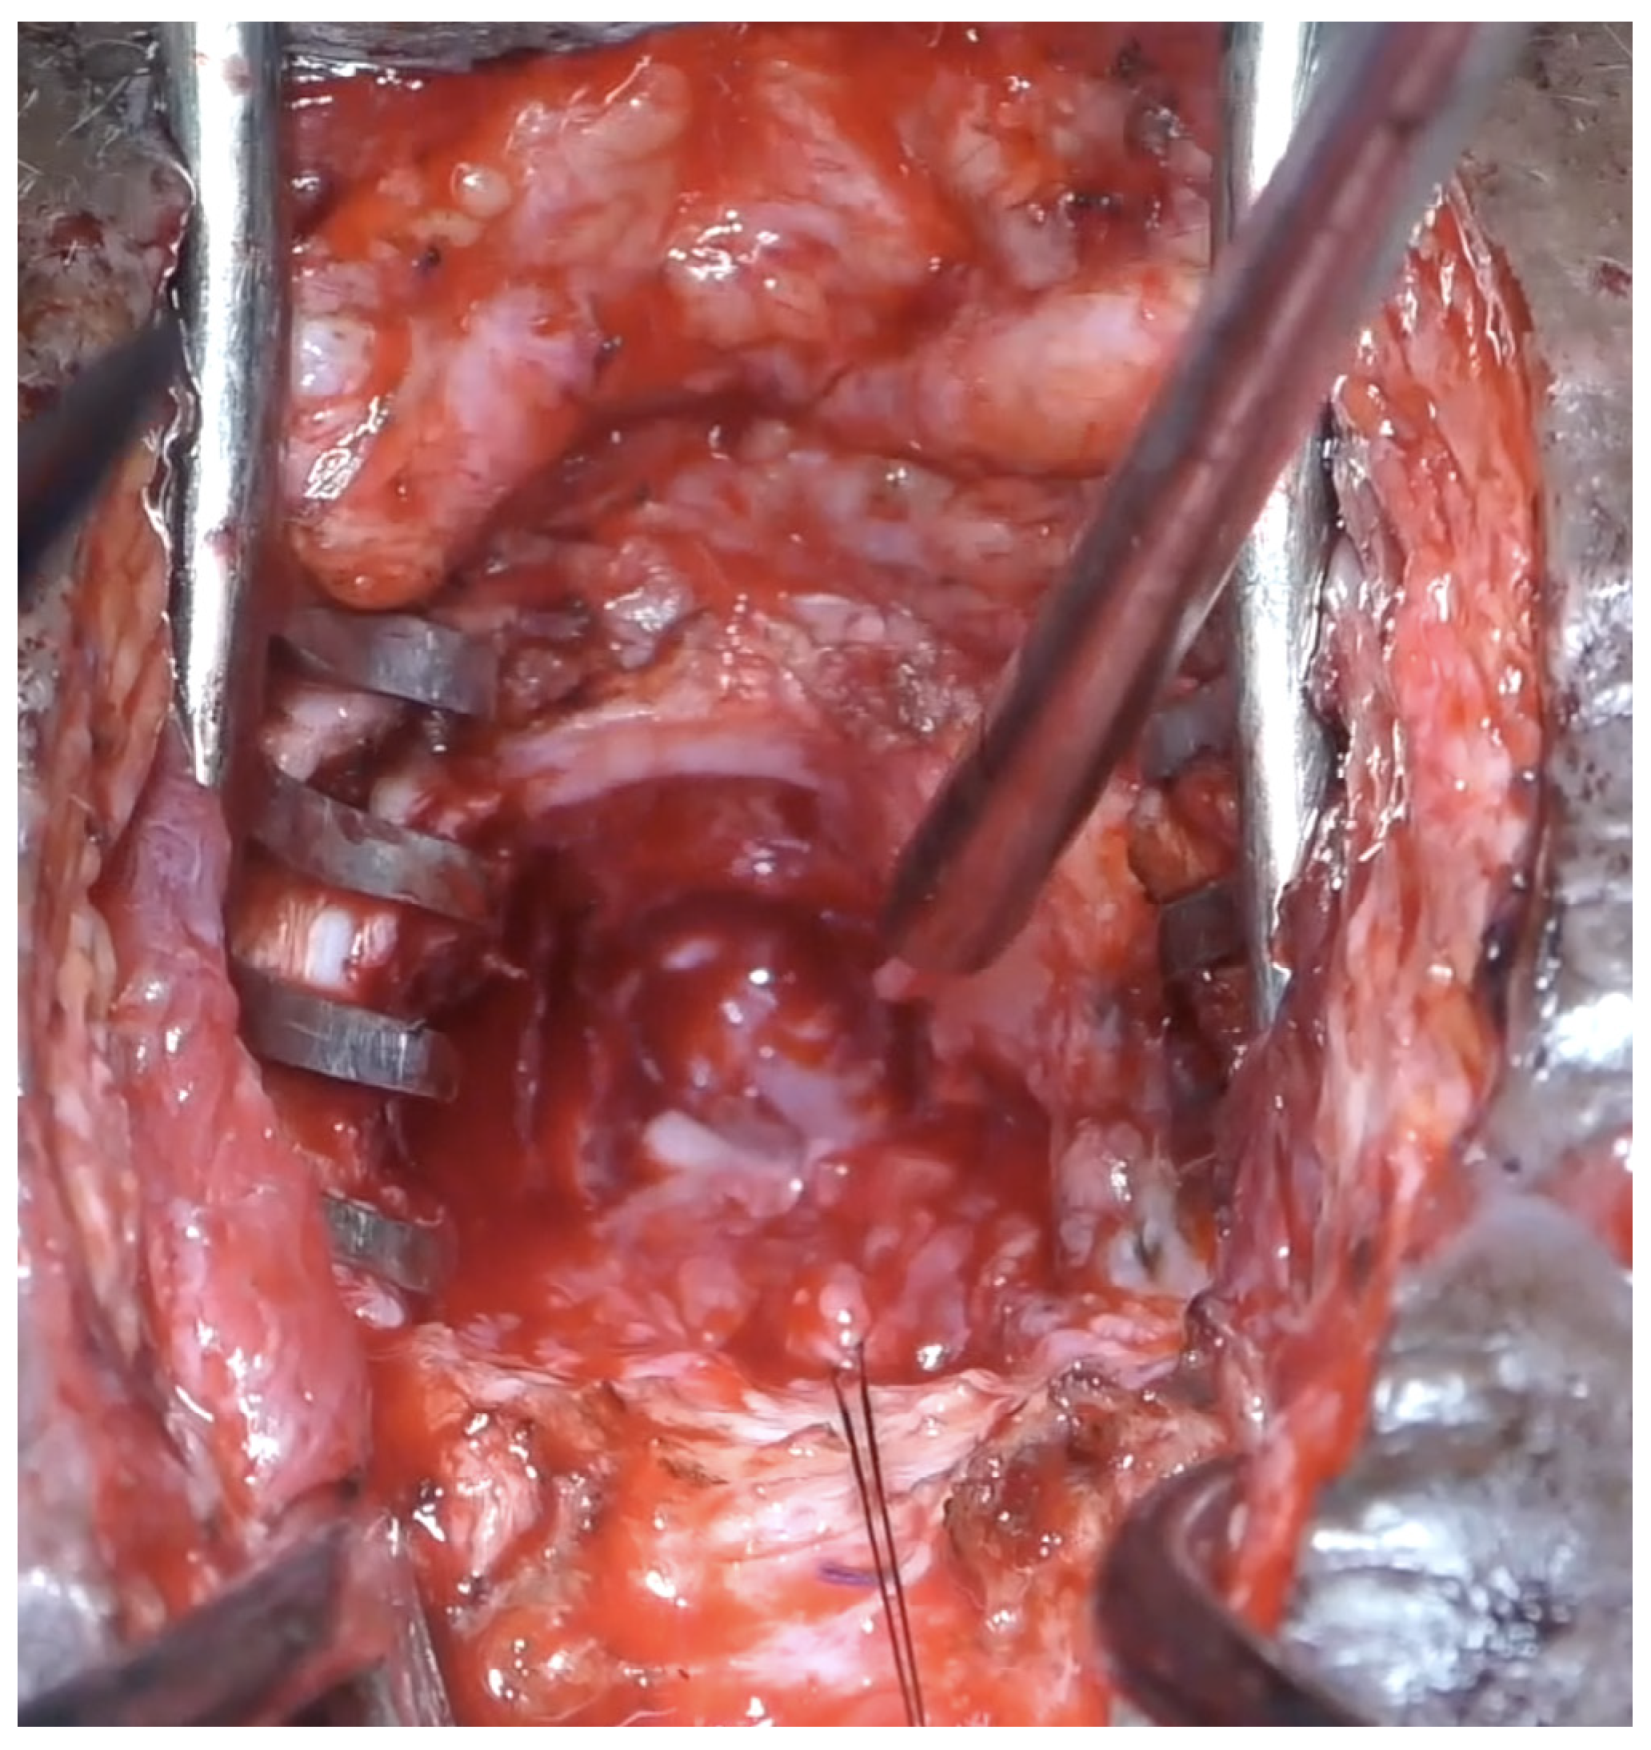

2. Materials and Methods

2.1. Approach

2.2. Transection at Bladder Neck

2.3. Transection at Proximal Urethra

2.4. Transection at Mid Urethra

2.7. Vaginal Injury